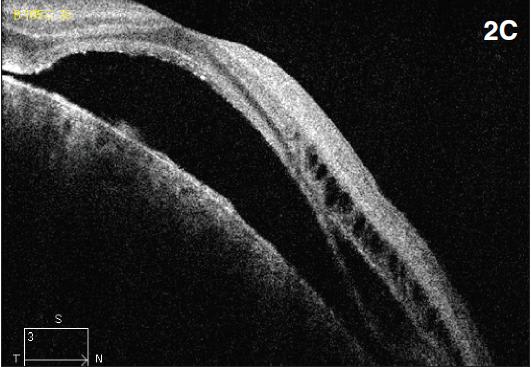

Figure 2. Diffuse choroidal hemangioma. The patient was a nine-year-old boy with history of Sturge-Weber syndrome, referred due to decreased vision (20/200) and subretinal fluid in the right eye. The fundus exam revealed retinal pigment epithelium mottling around the optic nerve with a surrounding cuff of subretinal fluid (A). B-scan ultrasonography demonstrated a solid, highly echogenic lesion, with diffuse choroidal thickening (B). OCT showed subretinal fluid with cystic spaces in the outer retinal layers (C). One year after treatment with external beam radiotherapy (20 Gy in 10 fractions, 2 Gy/fraction), the fundus exam revealed a regressed hemangioma (D). Tumor regression was confirmed by B-scan ultrasonography (E). Concomitant resolution of subretinal fluid was noted on OCT (F). Visual acuity improved to 20/60.

B-scan ultrasonography demonstrates solid, highly echogenic lesions, with diffuse choroidal thickening (Figure 2b), and high internal reflectivity on A-scan. Early hyperfluorescence with persistence of hyperfluorescence through the late phases of the angiogram are seen with fluorescein angiography. Similar findings are observed on ICG, with a characteristic lacy intrinsic vascular pattern, with a diffuse distribution.16 OCT may be used to confirm the presence of subretinal fluid (Figure 2c).

External beam radiotherapy (Figures 2d-f), plaque radiotherapy, proton beam radiotherapy and PDT are among the modalities that have been used for the management of these lesions.17-19 Resolution of subretinal fluid and tumor regression have been documented with use of lowdose radiotherapy or proton beam irradiation.20 Schilling et al. reported the results of 15 patients treated with lesionsparing radiation (20 Gy, 2 Gy/fraction) with a mean follow-up of 5.3 years. Complete resolution of exudative detachment was achieved in all cases. Visual acuity was improved in seven patients.18